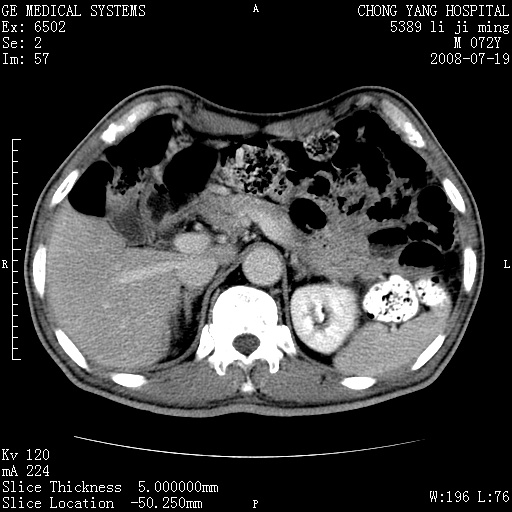

以下是引用zjzjr在2008-7-19 20:57:00的发言:[br]胰头增大,边缘模糊,周围可见渗出影,右侧肾前筋膜增厚.支持胰腺炎.

以下是引用yangyudong333在2008-7-20 6:56:00的发言:[br]胰腺增大尤以胰头明显,边缘模糊,周围可见渗出影,右侧肾前筋膜增厚,肠管於涨.支持胰腺炎

以下是引用不学无术在2008-7-19 23:15:00的发言:[br]胰腺增大尤以胰头明显,边缘模糊,周围可见渗出影,右侧肾前筋膜增厚,肠管於涨.支持胰腺炎